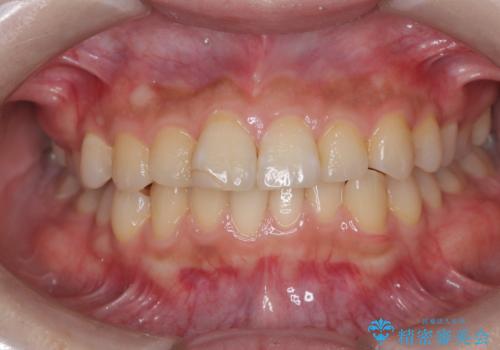

汚れを落としてからオフィスホワイトニングを!

- まずはアフローをして汚れを落とし、オフィスホワイトニングエクセレントを行いました。

エアフローで汚れを落としてピカピカの状態でオフィスホワイトニングを行うと、より効果的です。